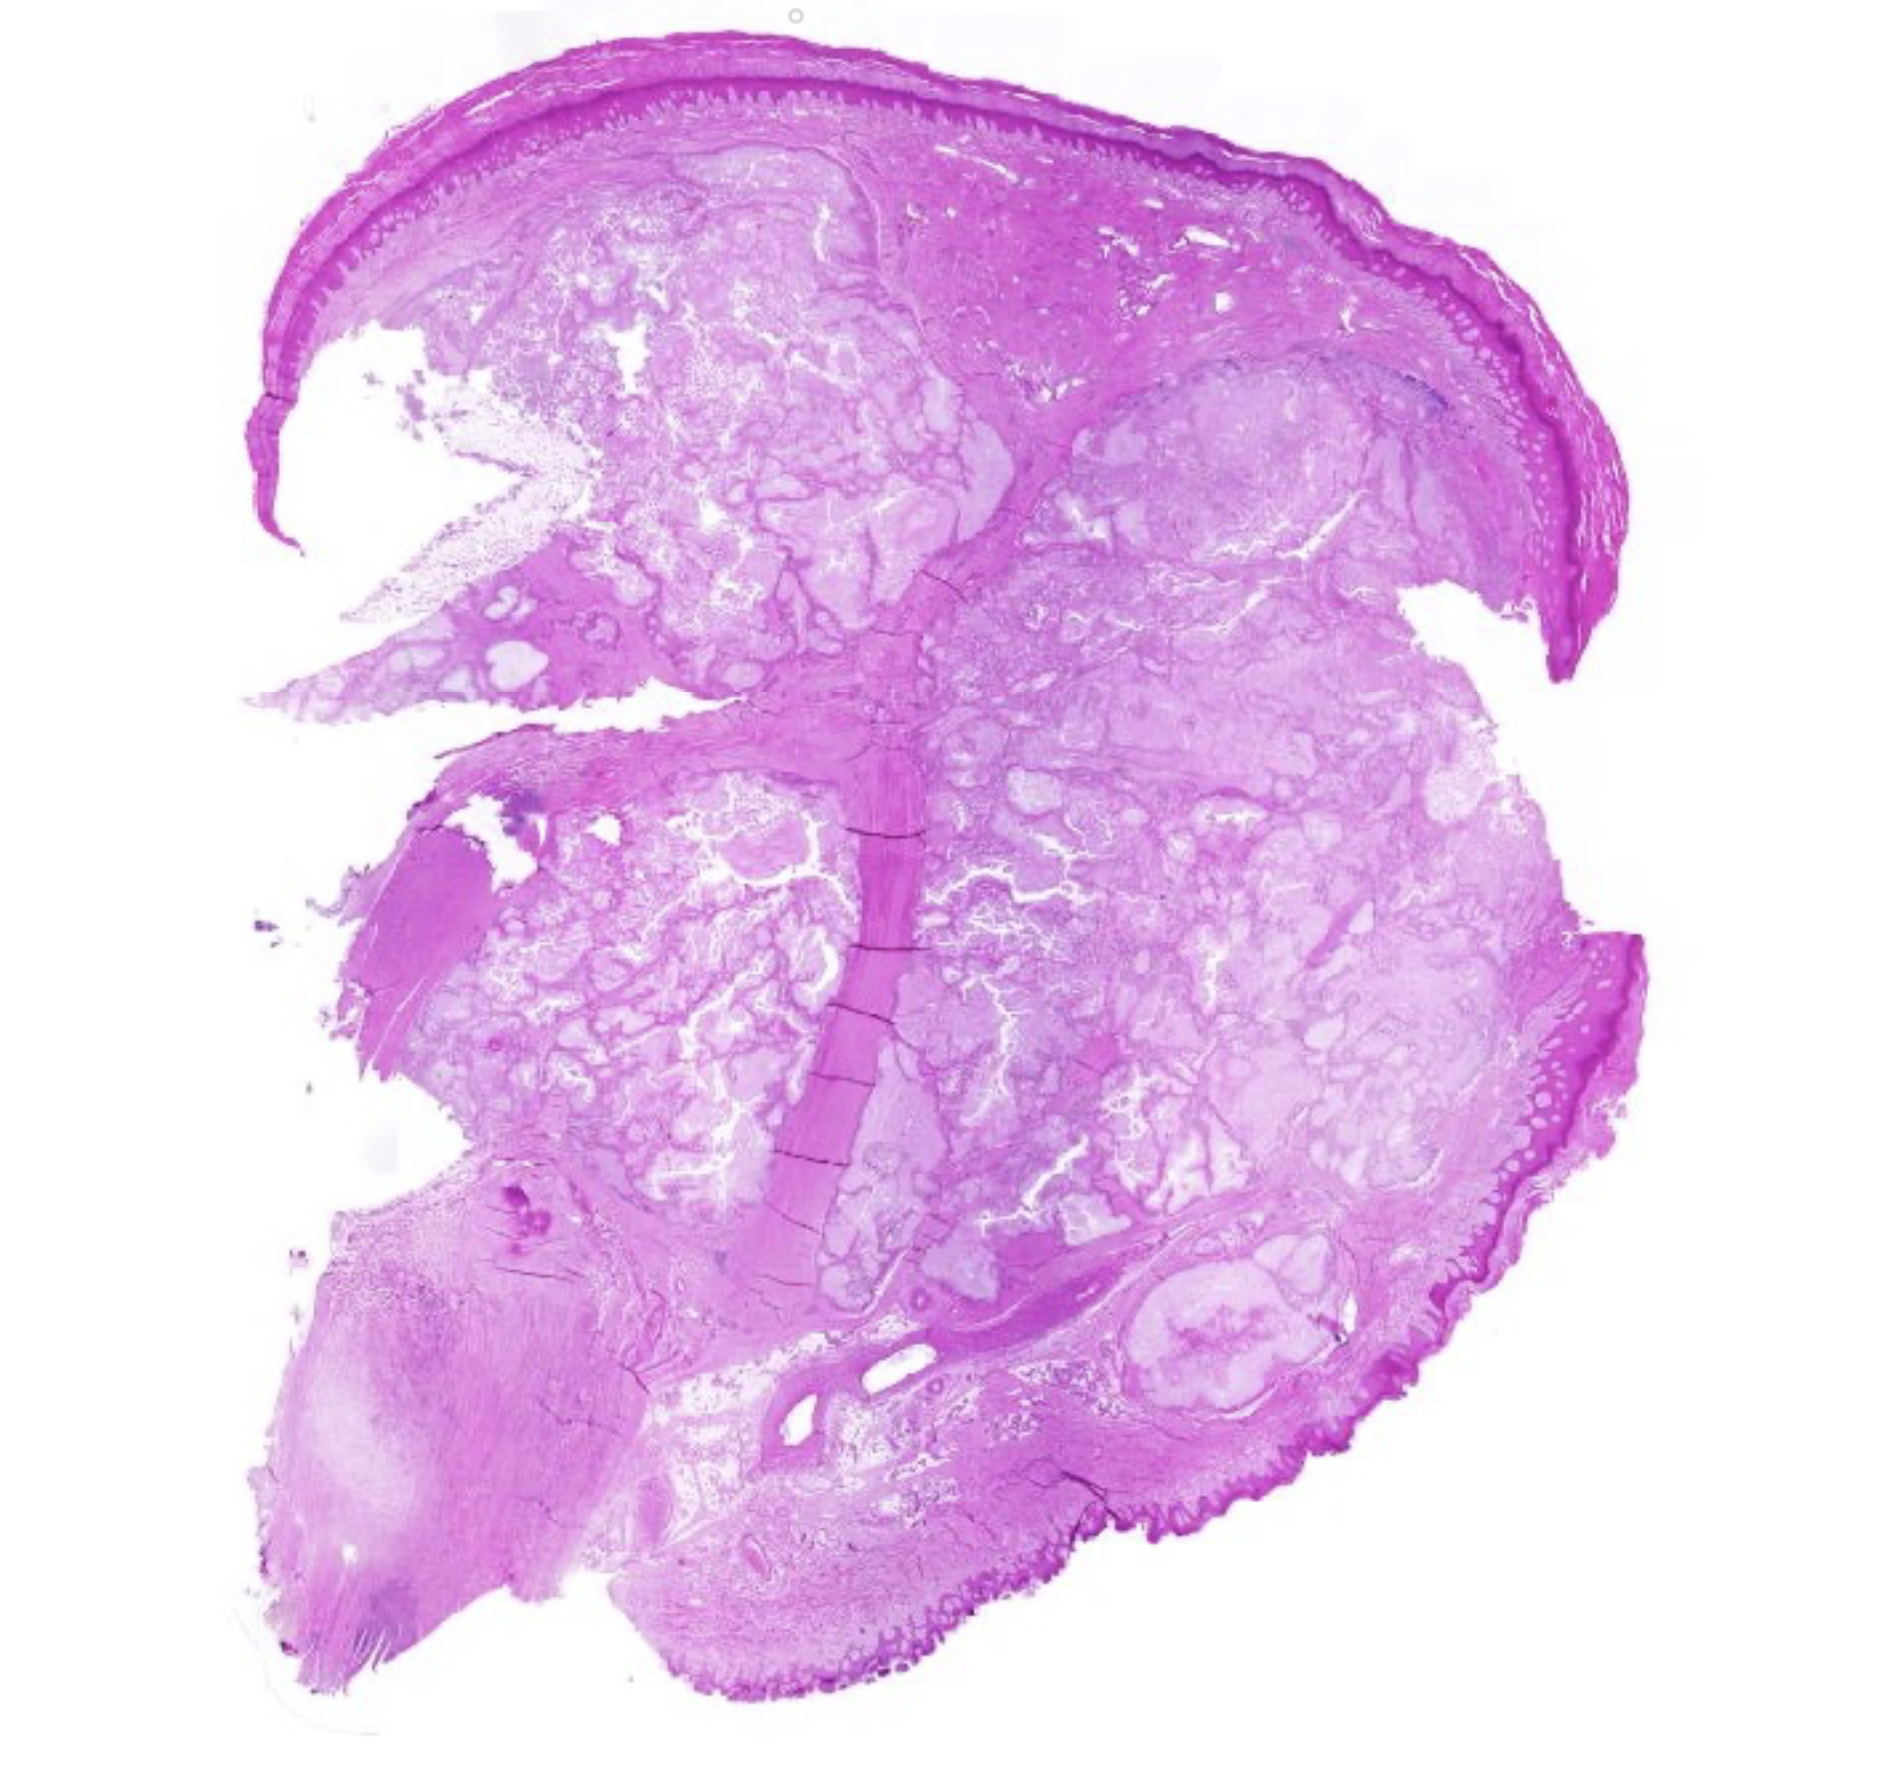

welk preparaat

levercirrose met macrovesiculaire steatose

benamingen van boven naar beneden (levercirrose)

kapsem van Glisson

Hepatocyten

Bindweefsel

chronische ontsteking lever gevolgen

fibrose en verlies hepatocyten

—> nodules

= cirrose

histologische tekens van ontsteking lever

toename in sclereus bindweefsel

ganaalkanaaltjes

vascularisatie